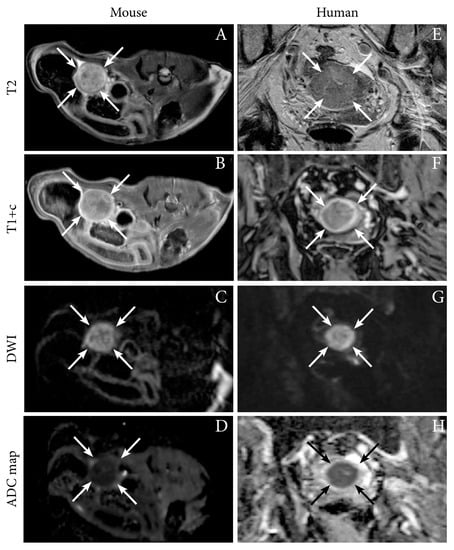

| MRI T1, T1+C, T2, DW, ADC | Present preclinical imaging findings using multiple imaging techniques | Tumor can be delineated using anatomic sequences and exhibits restricted diffusion with low ADC-values | Ishikawa cells, orthotopic, NSG mice | [12] |

| Tumor heterogeneity and vascularity | DW- and DCE MRI | DW- and DCE-MRI are valuable supplements to conventional diagnostic MRI sequences [22,23]. | DCE-parameters (Fb, Ktrans and Ve) are lower in tumor than normal myometrium, tumor ADC is negatively correlated to tumor volume [23]. | DWI (ADC value is negatively correlated to Ki67 proliferation index) to assess treatment response by PI3K-inhibitor perifosine and cisplatin in ovarian xenografts [72]. DWI (↑ADC value) and DCE (↑Ve ) to demonstrate BEZ235 (dual PI3K/mTOR inhibitor) treatment response in ovarian xenografts. [73]. |